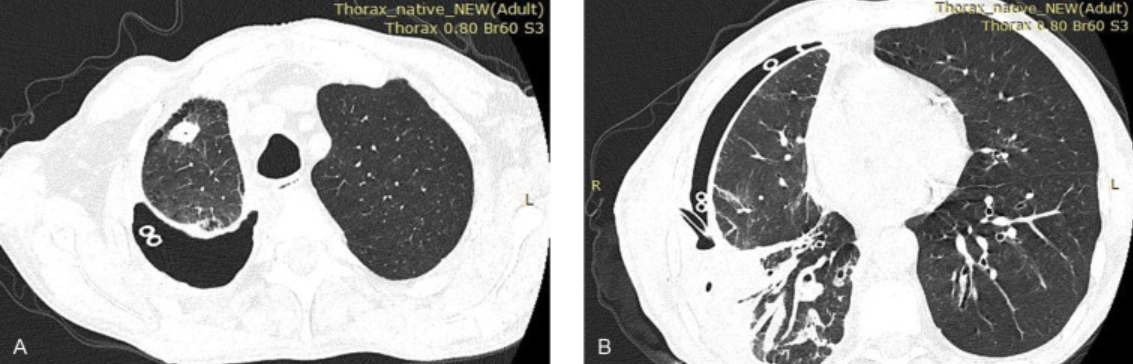

Chest X-rays or CT scans:

- How it works: Chest X-rays use high doses of ionizing radiation to create 2D images of the chest. CT scans are much more sensitive and use a series of X-rays combined with computer processing to give more detailed 3D images of the chest.

- What it’s used for: To locate and identify blockages and any structural changes, such as infections or inflammation1.